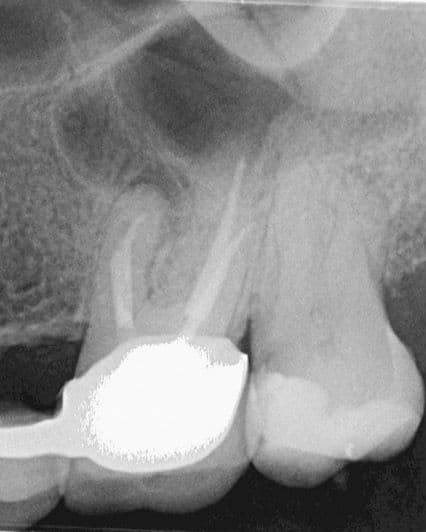

Kontrolden 14 ay sonra (2025 Nisan) hastamız bu sefer 26 numaralı dişinde ağrı şikayeti ile kliniğimize başvurdu İlgili dişe sonunda retreatmant tedavisine başlanabildi. (Şekil 4).

(Şekil 4) 2025 Nisan meziobukkal kök ucunda daha da genişlemiş periapikal lezyon